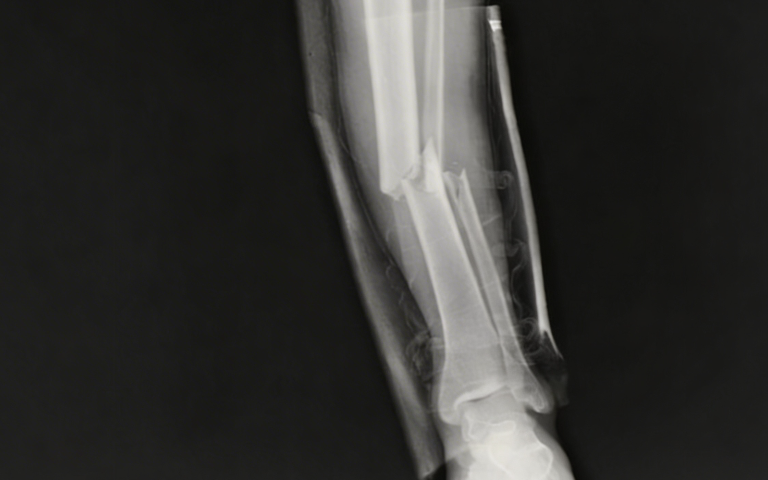

Intramedullary nailing involves placing a strong metal rod inside the hollow centre of a fractured bone, commonly the femur, tibia, or humerus. This internal support holds the bone in correct alignment while it heals, preventing deformities or improper union. Compared to traditional plates and screws, this method is less invasive, causes minimal soft tissue damage, and allows for earlier rehabilitation. Consultation with a skilled Orthopaedic Specialist in Islamabad ensures this approach is appropriate for the fracture type and patient’s overall health.

During intramedullary nailing, the surgeon makes a small incision to insert a specially designed metal rod along the central canal of the fractured bone. Screws or locking devices at each end stabilise the rod, maintaining perfect alignment during the healing process. The procedure is performed under strict sterile conditions with advanced imaging guidance, allowing an Orthopedic Surgeon in Islamabad to achieve precision and long-term stability while minimising trauma to surrounding tissues.